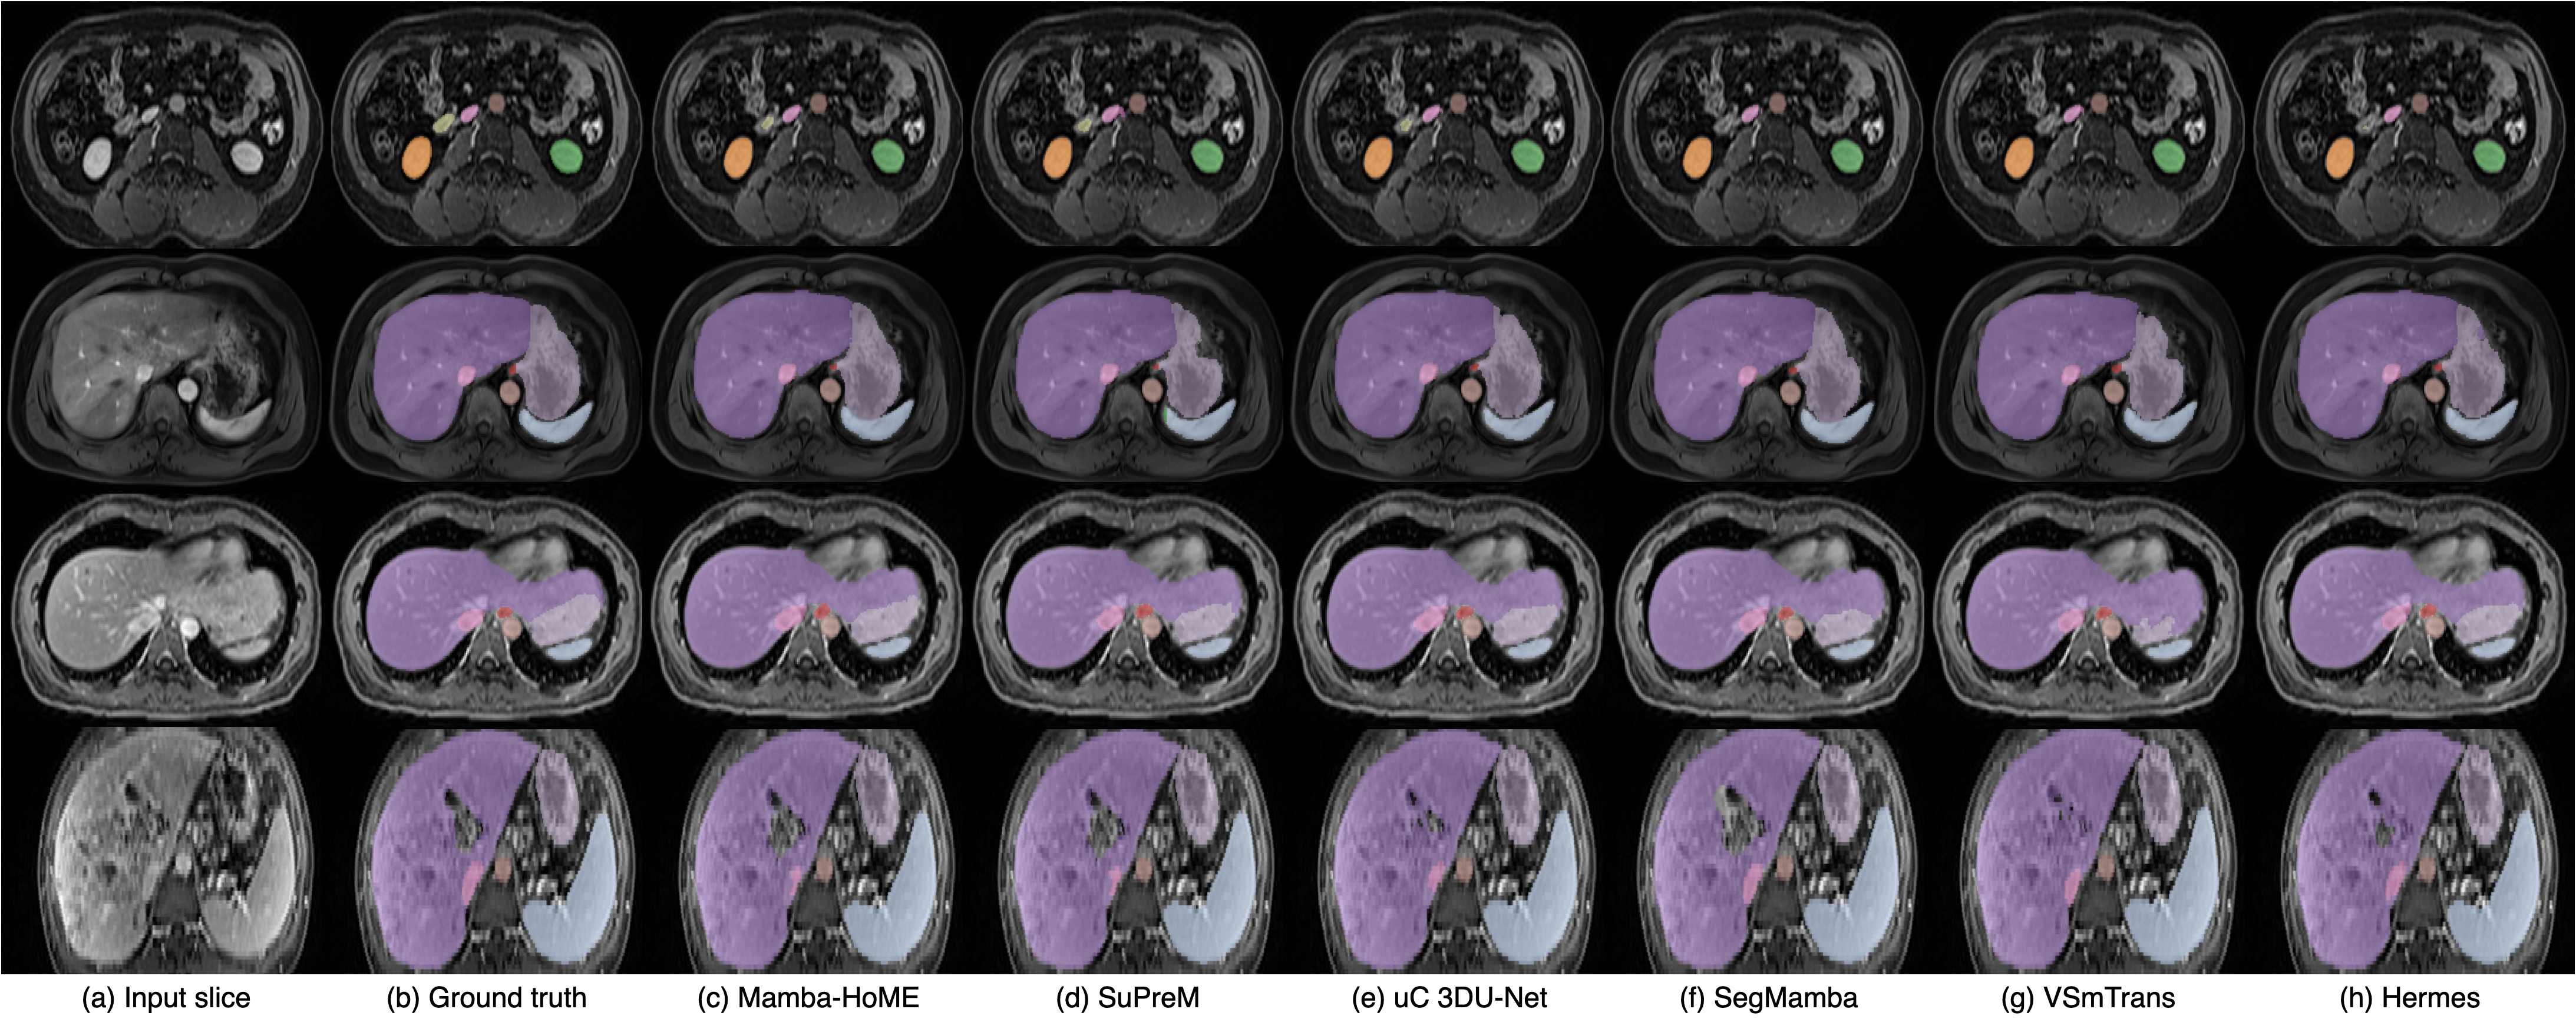

Qualitative results. Figure 2 presents a qualitative comparison of our proposed Mamba-HoME method against the five top-performing baselines across three primary 3D medical imaging modalities: CT, MRI, and US. These modalities exhibit different organ contrasts, noise levels, and resolutions. Mamba-HoME demonstrates consistent improvements in segmentation quality across these scenarios. In the first row, it effectively handles small and closely located structures, showing precise boundary delineation while reducing common artifacts seen in baseline predictions. The second row highlights its capability to accurately segment organs of various shapes and sizes, even under low image quality conditions, with reduced susceptibility to over- or under-segmentation. The third row illustrates Mamba-HoME’s robustness in handling noisy and low-resolution data, maintaining clear and anatomically accurate boundaries.

Figure 2: Qualitative segmentation results from top to bottom: CT, MRI, and 3D US. From left to right, each column shows the input slice, ground truth, the proposed Mamba-HoME, and the five next best-performing methods.